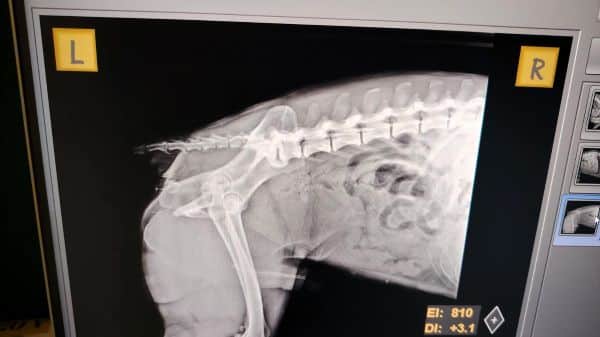

MATEI wurde vom Auto angefahren und am Straßenrand einfach liegen gelassen. So wurde er heute gefunden. Bei der Untersuchung kam heraus, dass seine Wirbelsäule verletzt ist. Die Ärzte sind zuversichtlich, dass man ihm mit einer Operation helfen kann und seine Verletzungen heilen werden. Daher wurde er nun in die Tierklinik nach Bukarest gebracht.

| zur Besonderheit: | hatte Autounfall, aktuell in Clinic |